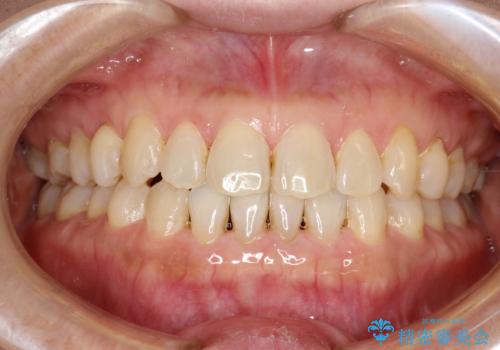

前歯の隙間 インビザラインによる目立たない成人矯正

- 前歯の隙間を気にされて来院されました。

インビザラインにて、目立たずに矯正治療を行うこととしました。

歯と歯の間にある隙間を閉じるのは、インビザラインでもしっかり治療できます。